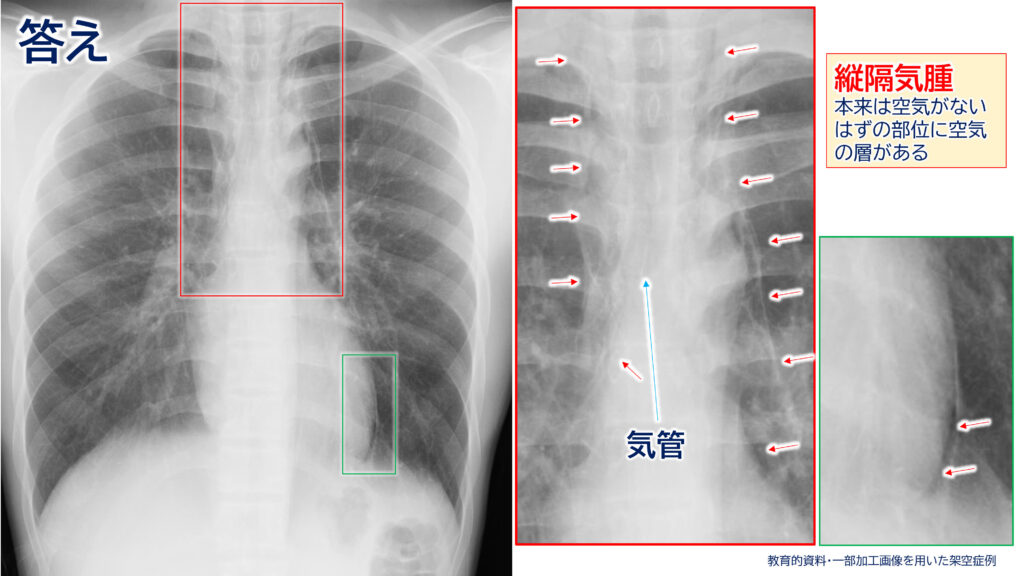

本症例は……

”縦隔気腫(じゅうかくきしゅ)”です。

縦隔気腫とは、

両肺を隔てている「縦隔」という領域に空気が入り込んでしまう状態です。

縦隔には、

心臓や大血管、気管、食道などが集まっており、本来この領域には気管内や食道内以外には、空気は存在しません。しかし、何らかの原因で空気が縦隔内に広がることで発症します。

<答えの解説>

所見は実際にはAとCの両方に認められますが、今回は「主な」病変部位を問う趣旨の問題でしたので、正解はAとなります。

(画像分割の都合上、このような形式となりました。)